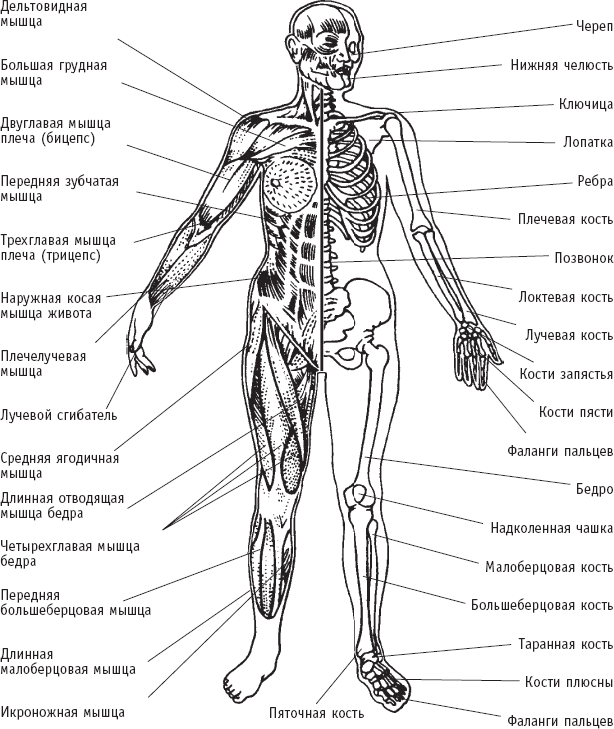

Опорно-двигательный аппарат

Основную массу тела человека, около 75 % общего веса, составляет опорно-двигательный аппарат, в который входят мышцы, кости, суставы, сухожилия, связки и хрящи. Опорно-двигательный аппарат придает телу человека определенную форму, благодаря ему он может стоять прямо и передвигаться.

Некоторые мышцы и кости человека

Костный скелет – часть опорно-двигательного аппарата – является остовом для различных органов и тканей, он защищает от повреждений такие жизненно важные органы, как головной и спинной мозг, сердце и легкие. В костях накапливаются необходимые организму минеральные вещества: кальций и фосфор. Кости содержат костный мозг, в котором образуются все клетки крови – эритроциты, лейкоциты и кровяные пластинки.

К костям прикрепляются мышцы, которые за счет сокращения и расслабления волокон делают возможными движения различных частей тела. Ряд мышц расположен внутри органов и не связан с костями. При сокращении этих мышц осуществляется работа основных внутренних органов и обеспечиваются жизненно важные процессы в организме: перекачивание крови из сердца в кровеносные сосуды, прохождение пищи через желудочно-кишечный тракт и др. Благодаря сокращению мышц выделяется тепло и поддерживается нормальная температура тела.